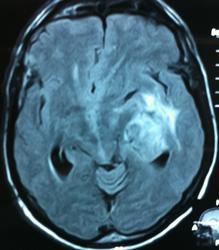

Начало вот здесь http://www.radiomed.ru/cases/kt-gms-obemnoe-obrazovanie-levoi-gemisfery-bolshogo-mozga-vnutrizheludochkovaya-meningioma. Пациент оперирован (меня сначала дезинформировали по поводу операции), перед операцией состояние ухудшилось, возникла правосторонняя гемиплегия, которая осталась и после декомпрессии. МРТ, КТ снимки и выписку предоставила супруга пациента, снимал на iphone, простите за качество, дисков с исследованиями не записывали. Надеюсь вопрос по данному случаю исчерпан.

Вот "цветочки":

T1+C

Т2

FLAIR

Изначально по КТ я так предпологал, а теперь на 100% уверен, разве МРТ это не показало? Гистологически - менингиома, опухоль мозговой оболочки. Покажите, пожалуйста, образование где-нибудь прилежит к костям, где есть мозговая оболочка? Я не вижу, зато отчетливо вижу в левом боковом желудочке из оболочек сосудистого сплетения. Что вас еще смущает? По-моему, предостаточно фактов, чтобы развеять все сомнения.

Мне видится так. Иначе в данной локализации просто неоткуда расти оболочечной опухоли. На контрольной КТ, после декомпрессии, когда срединные структуры стали действительно срединны, правое обызвествленное сосудистое сплетение видно отчетливо, а левое, где оно? Ведь если бы образование компремировало, то после операции, когда часть мозга пролабировало в трепанационное отверстие мы бы увидели и левое сосудистое сплетение, но оно интимно связано с образованием и даже "потянулось" за ним в сторону декомпрессионного отверстия, потому что это и есть "росток" откуда выросла опухоль.

У меня вопрос (извините, если тупой - я-не волшебник, я только учусь=) - мне кажется, что в центре образования есть участки пустоты потока (сосуды), а разве менингиома склонна к такому неоангиогенезу? просто прочитала все вышенаписанное, вроде полностью согласна, но как вариант закралась мысль о сосудистой опухоли из сплетения бок.желудков. Если я совсем не права, прошу пояснить. Хочется все понимать уже на первых годах работы.) Заранее благодарю.

Там начало. Мысль о сосудистой опухоли-это вы подразумеваете кавернозную ангиому? Она не копит контраст. На первых годах работы вам в помощь четырехтомник "Диагностическая нейрорадиология" В.Н. Корниенко, И.Н. Пронин, а также их дополнение "Контрастирование в нейрорадиологии". Я думаю опыт НИИ Бурденко не маленький в плане визуализации образований головного мозга, там кстати и сможете купить эти книги с автографами, в сети стоимость 4 томов - 25 т.р.